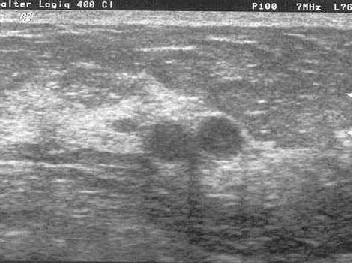

Mit den neuen hochauflösenden Geräten lassen sich auch kleine Befunde darstellen:

Diagnose: Fibroadenom (=gutartig)

Diagnose: 2 kleine Fibroadenome (=gutartig)